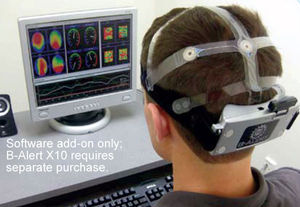

... el estrés, la confusión, el compromiso y la carga de trabajo, utilice el sistema B-Alert X10 con el software Cognitive State. Las métricas del software clasifican los datos de los sistemas de EEG inalámbricos B-Alert. ...

Biopac Systems